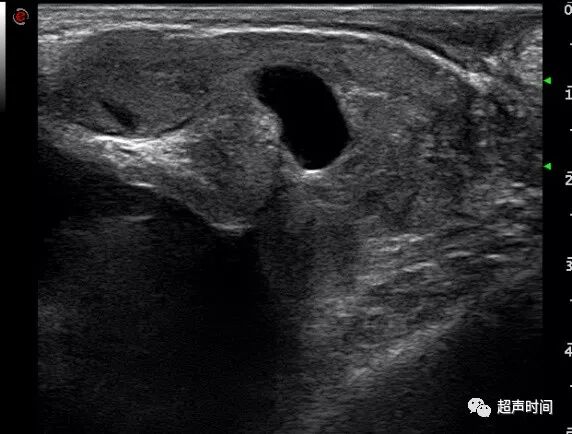

射精管囊肿:位于前列腺中部,横切面呈圆形,纵切面呈椭圆形暗区,内径约 5 mm左右,很少超过 10 mm(图 3)。

图 3 经直肠线阵超声示射精管囊肿。患者 35 岁,血精伴排尿痛,射精管囊状扩张,精囊腺内径 1.6 cm